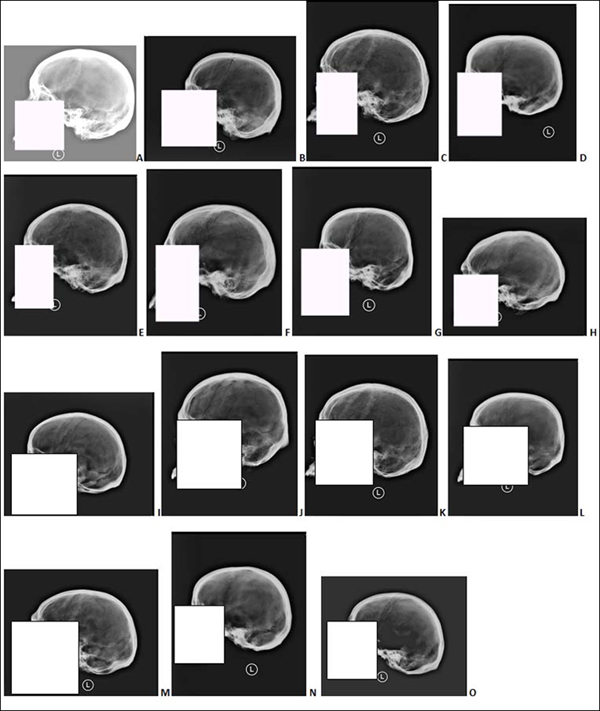

Specifically, only 56 percent of forensic anthropology Ph.D.s (the bone experts) could correctly match two images of the same skull, based solely on the “cranial vault outline” of the skull – the side profile of the skull running from just above the bridge of the nose to the point where the skull and neck meet.

下面,您将发现14个andemortem骷髅X射线和五个后骨折X射线。您需要将5次淘汰的X射线与适当的AnteMortem X射线匹配,有效地建立正面ID。让我们看看你是怎么做的!

第五个邮件X射线编号如下:1 =左上角,2 =左中心,3 =左下角,4 =右上角,5 =右下方。您可以单击图像以放大它们,答案位于帖子的底部。

Antemortem X射线